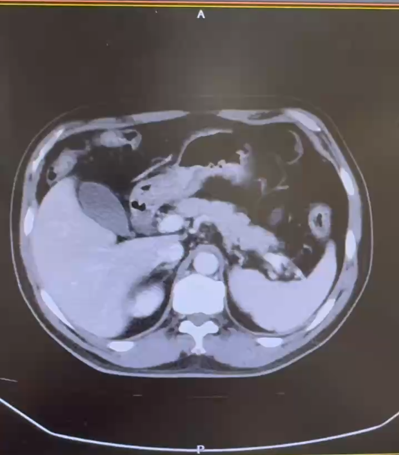

CT:1. 左肾下极占位性病变:肾 CA? 2. 双肺多发囊肿;3. 双肾小结石;4. 肝 S4 段强化灶;5. 肝多发囊肿。

2022.1 靶免联合新辅助治疗

新辅助治疗前

新辅助治疗后

治疗后复查 CT(2022.7):左肾透明细胞 CA 治疗后改变,肿块较前缩小,强化程度减低,左侧副肾动脉可见;余况同前。